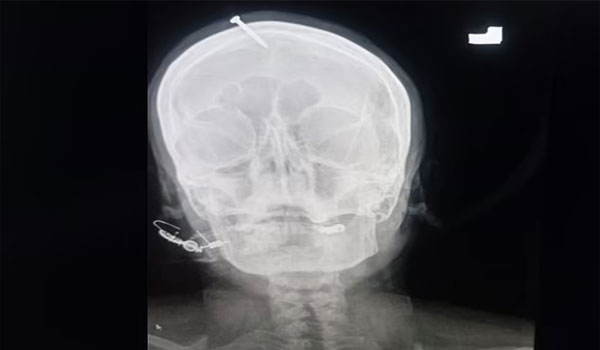

وتم إسعاف امرأة باكستانية حامل إلى مستشفى في شمال غرب مدينة بيشاور بعد أن تم دق رأسها بالمسامير، بناء على نصيحة الشامان “معالج ديني”، قال إن القيام بذلك سيضمن أنها ستلد صبيا.

وقال الدكتور حيدر سليمان، جراح الأعصاب المقيم، إن المرأة كانت “تنزف” عندما نُقلت إلى المستشفى وأن المسمار “تغلغل بعمق” في جمجمتها، مشيرا إلى أن أسرة المرأة حاولت إزالة المسمار في المنزل، ولكنهم فشلوا في ذلك ليتم نقلها إلى المنشأة الطبية، حيث تم إجراء عملية جراحية لها ومن ثم إعادتها.